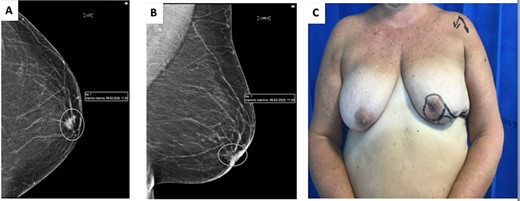

(A) image showing standard undermining of the lateral aspect remaining glandular tissue to facilitate advancement and rotation into central defect. (B) Insetting of modified Grisotti flap. (C) Closure of donor site and completion insetting of flap.

As per standard procedure [2], the undermining of the lateral remaining glandular tissue was then performed to facilitate the advancement, rotation and medialization of the glandular tissue in order to increase the projection of the breast (Fig. 3A and B). The patient had good aesthetic results and maintenance of an acceptable neo-nipple to IMF distance of 6.5 cm (Fig. 4).